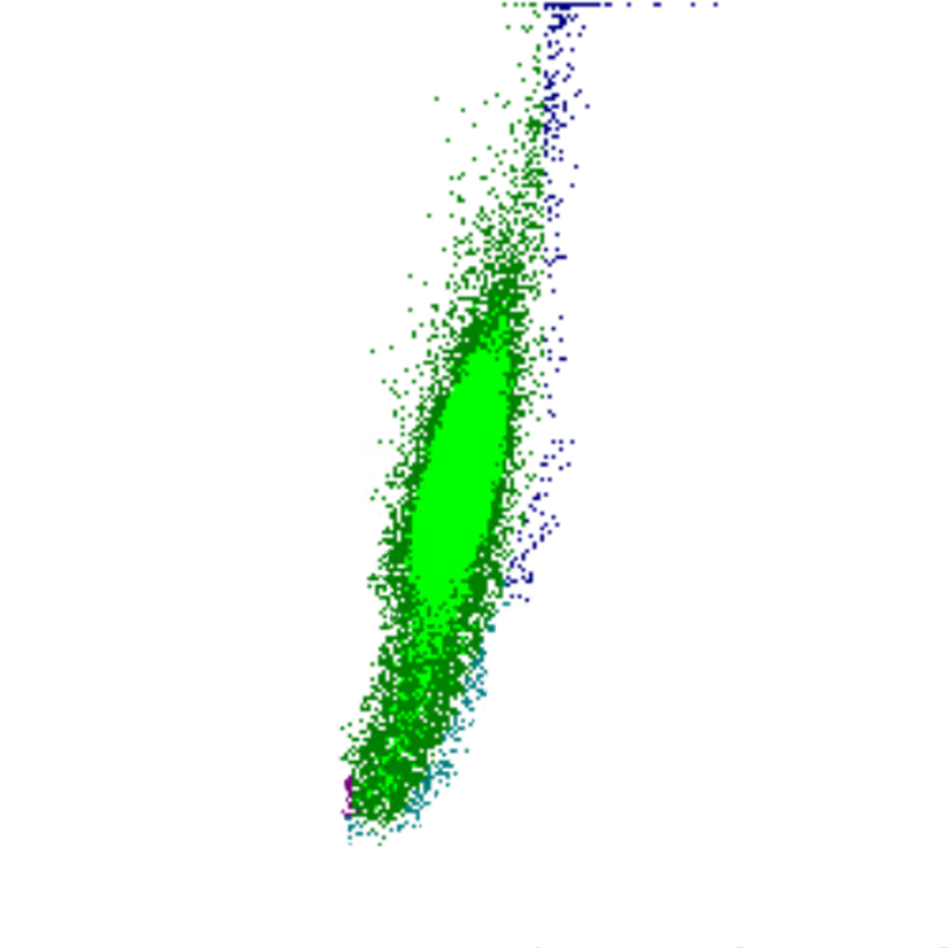

Selon les paramètres représentés l’un par rapport à l’autre, la combinaison de ces signaux détermine la position de chaque cellule sur le diagramme de dispersion. Cela génère des clusters caractéristiques pour les populations cellulaires normales et des motifs reconnaissables en cas d’anomalies.

Forward Scatter

Le FSC est une mesure de la taille cellulaire : des valeurs élevées de FSC indiquent des cellules plus grandes, tandis que des valeurs plus faibles correspondent à des cellules plus petites. Les plaquettes présentent le FSC le plus bas, tandis que les monocytes, les lymphocytes plasmocytoïdes et certains blastes figurent parmi les cellules les plus volumineuses.

FSC scatter

FSC faible

FSC élevé